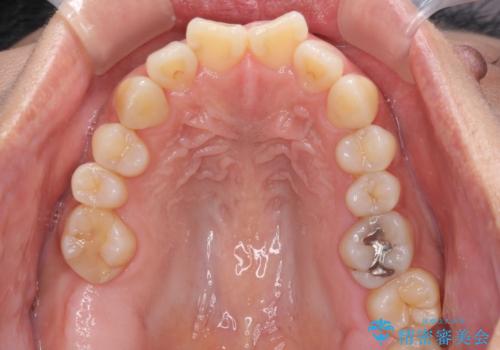

- 上下前歯の叢生を気にして来院された患者様です。

費用を抑え、期間もあまりかけずに治療をしたいとのことで、インビザライン・ライトを用いて矯正治療を行うこととしました。